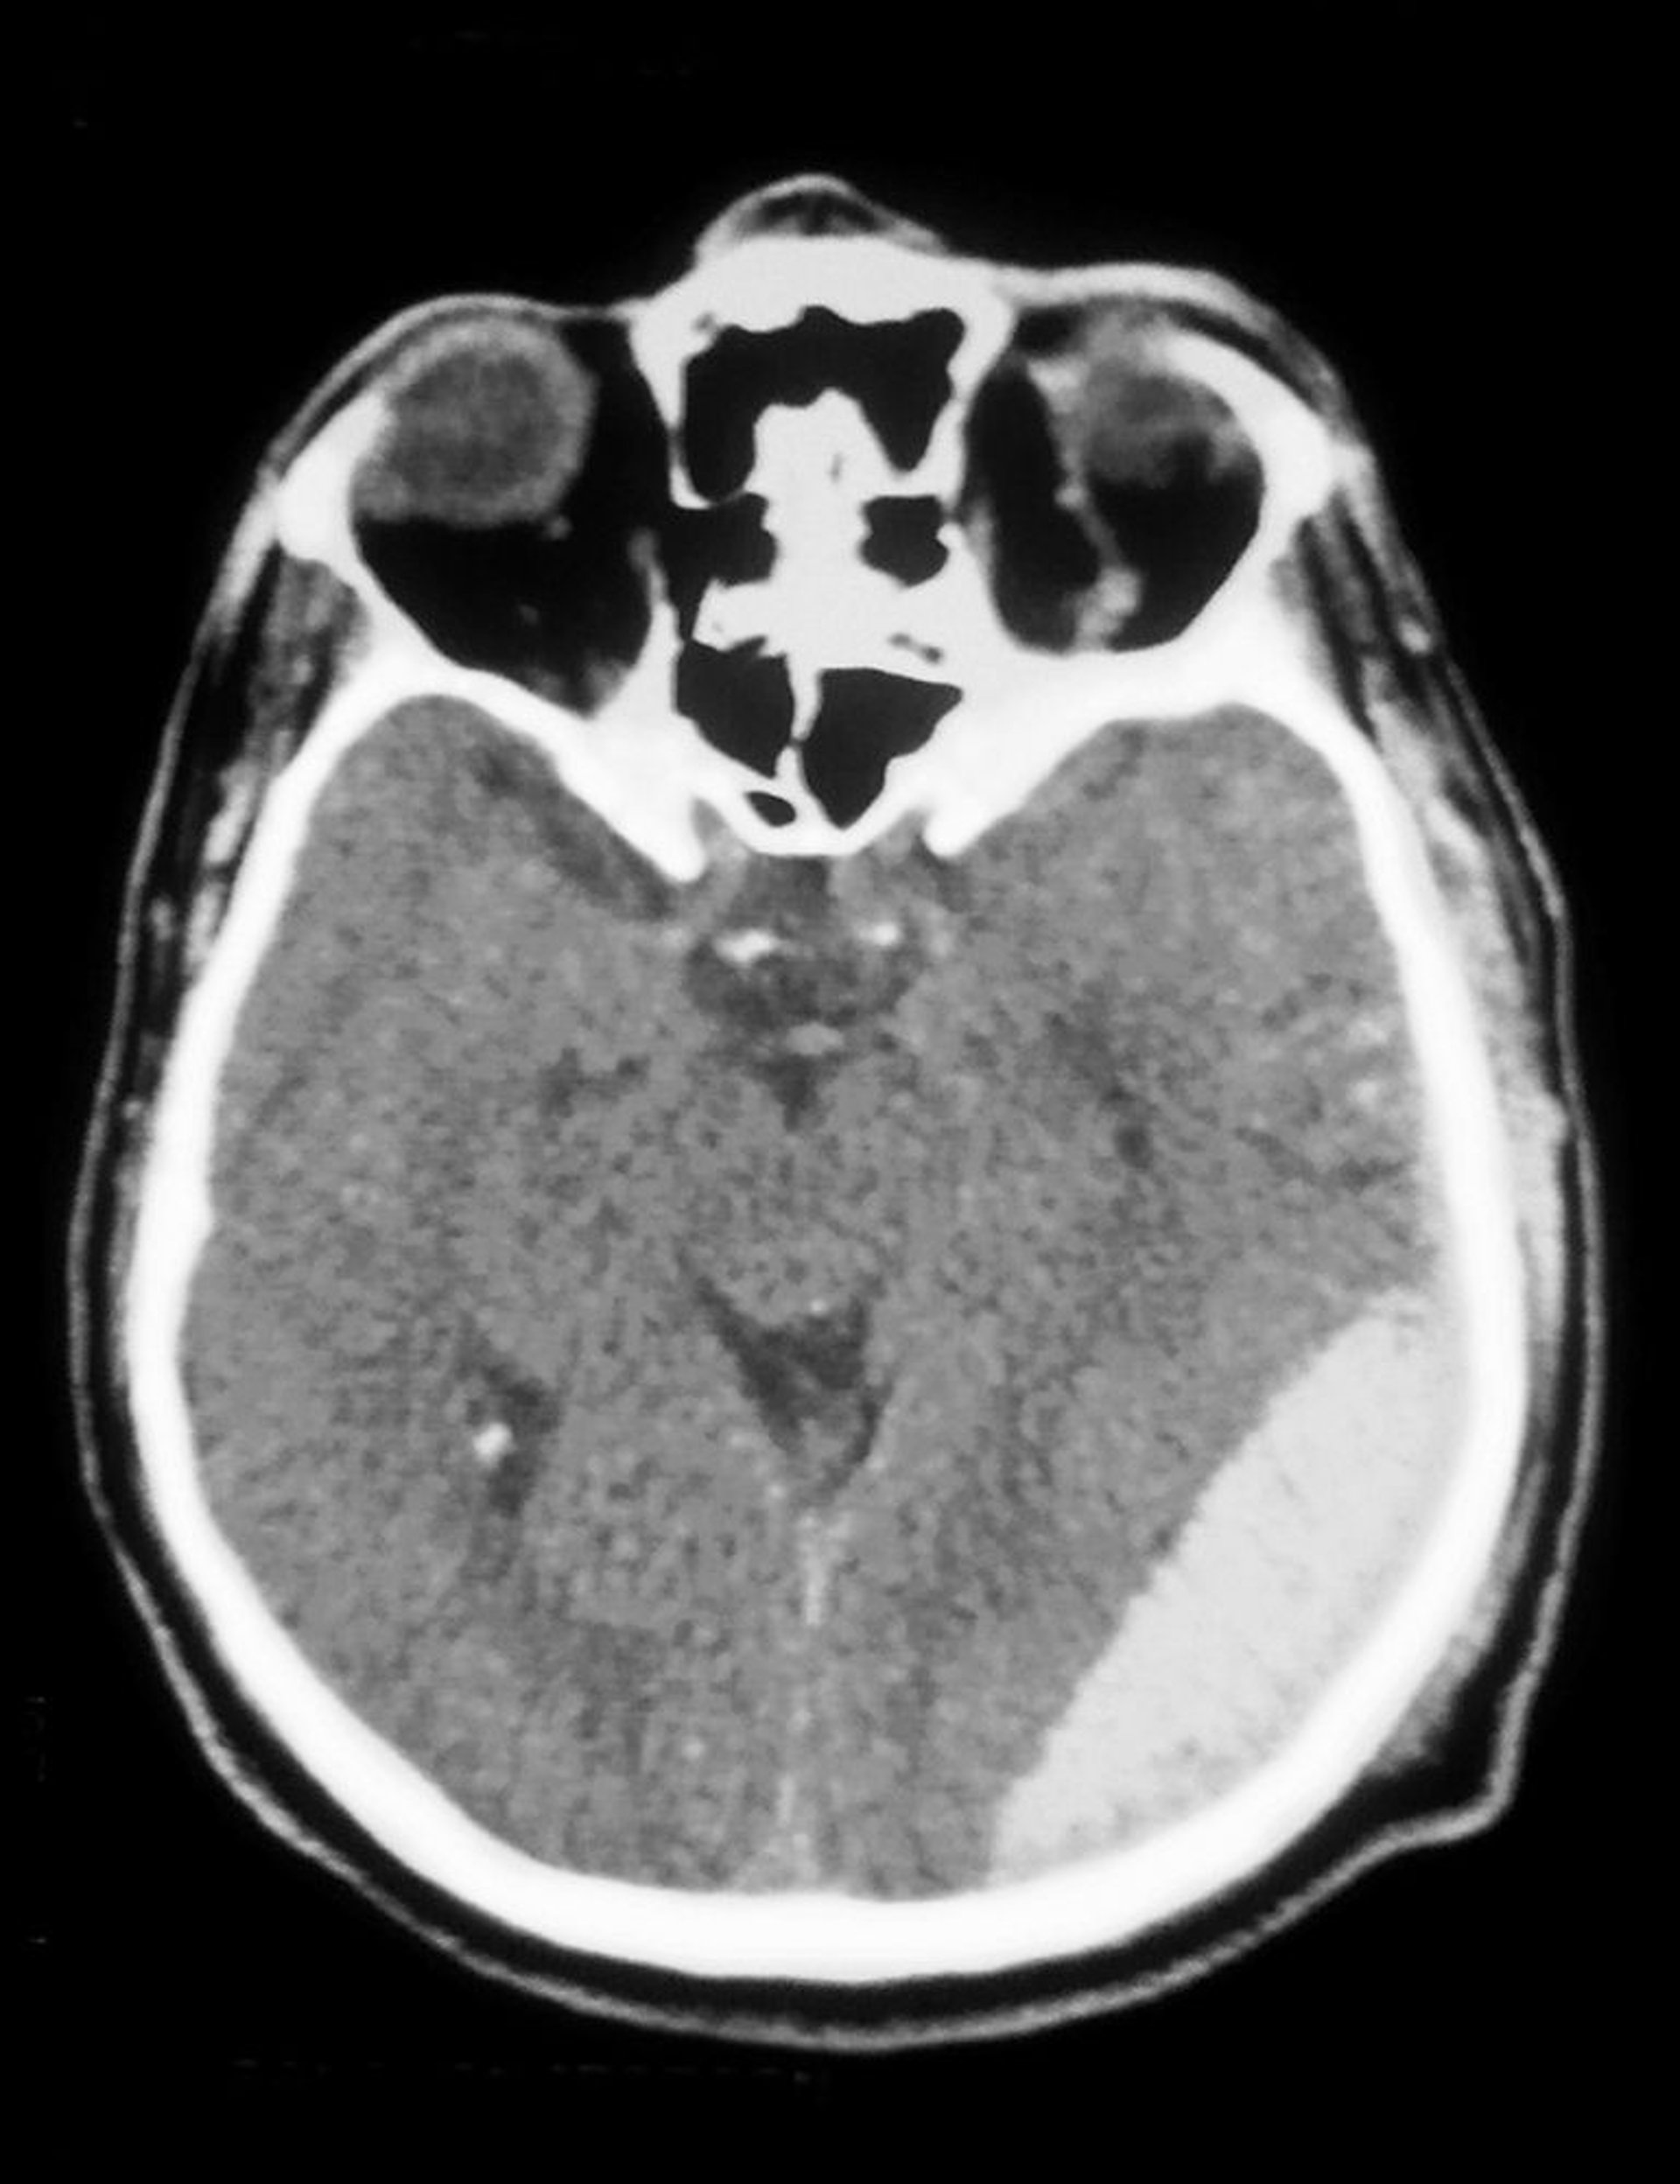

Ematoma epidurale

TC di un ematoma epidurale (opacità in basso a destra).

Cavallini James/BSIP/SCIENCE PHOTO LIBRARY